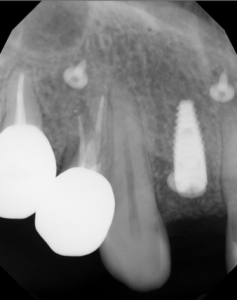

This video demonstrates implant placement in the esthetic zone combined with simultaneous guided bone regeneration (GBR). The case focuses on surgical decision-making, specifically how to determine when a staged approach is indicated versus when simultaneous implant placement and GBR can be predictably performed.

The procedure is presented step by step, including flap design and management, defect assessment, membrane selection and stabilization, flap advancement, and suturing techniques. Emphasis is placed on achieving tension-free closure and maintaining hard and soft tissue contours critical for esthetic success.